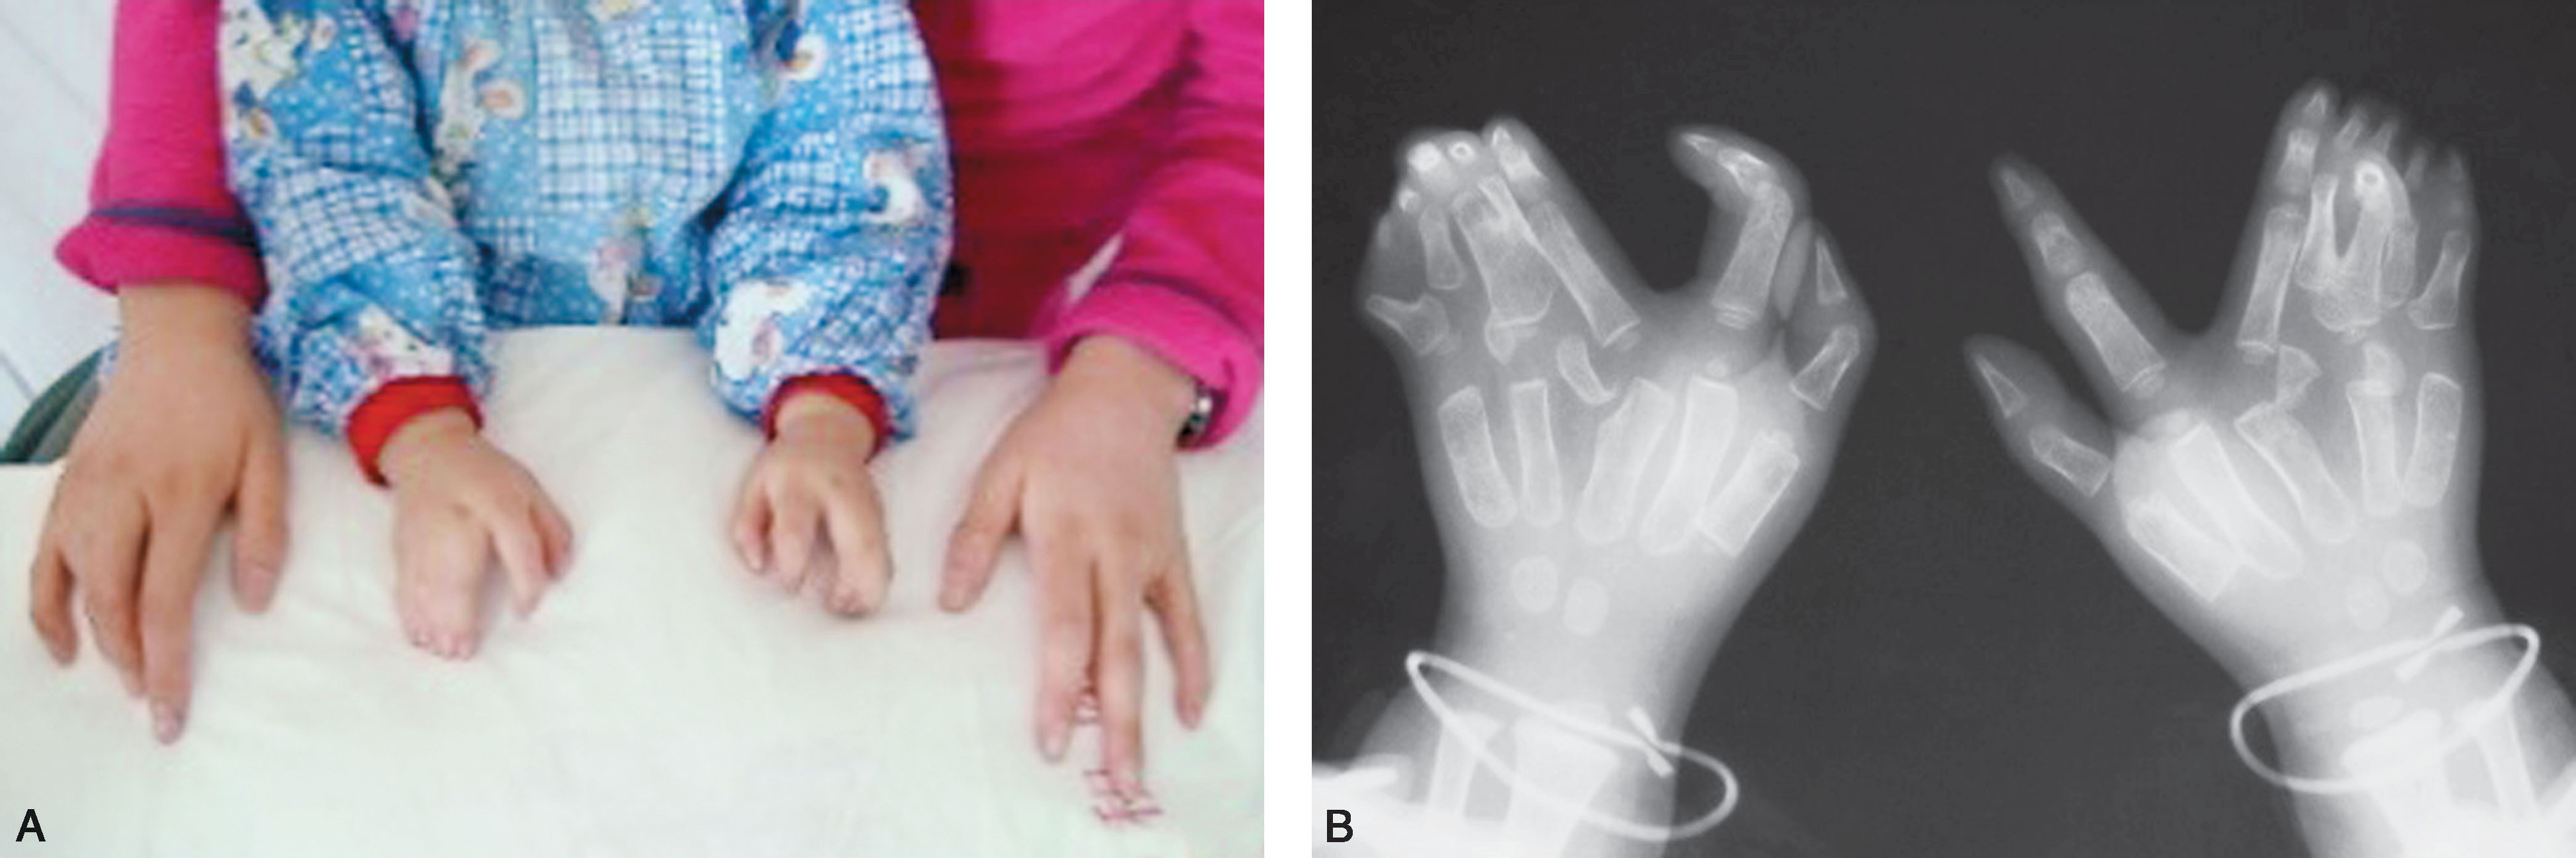

图2-5-2 中央型及尺侧多指并存病例2

A.复杂性多并指畸形,有家族遗传史;B.X 线片显示双侧小指多指,中指多指畸形,骨关节结构严重发育紊乱